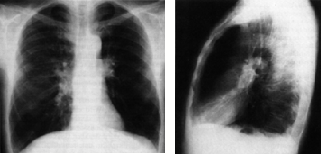

3.4.1 Silicosi

Inalazione di polvere ricca di quarzo per anni (minatori, sabbiatori) crea la silicosi.

3.4.1.1 Patogenesi

Delle particelle vengono fagocitate negli alveoli formando cellule di polvere. Processi enzimatici durante la decomposizione dei fagociti fanno crescere il tessuto connettivo in modo granulomatoso. Anche ad esposizione terminata la malattia pu progredire.

3.4.1.2 Sintomi

Non tipici, in stato avanzato dispnea e bronchite.

3.4.1.3 Diagnosi

Con radiografia.

3.4.1.4 Complicazioni

Tubercolosi in 30% dei casi, insufficienza cardiaca dx.

3.4.1.5 Terapia

Non specifica e palliativa (bronchite cronica, facilitazioni respiratorie)

3.4.1.6 Prognosi

Sfavorevole perch progrediente anche dopo aver interrotto lesposizione.

3.4.1.7 Prevenzione

Posto di lavoro, maschere, controlli radiografici.